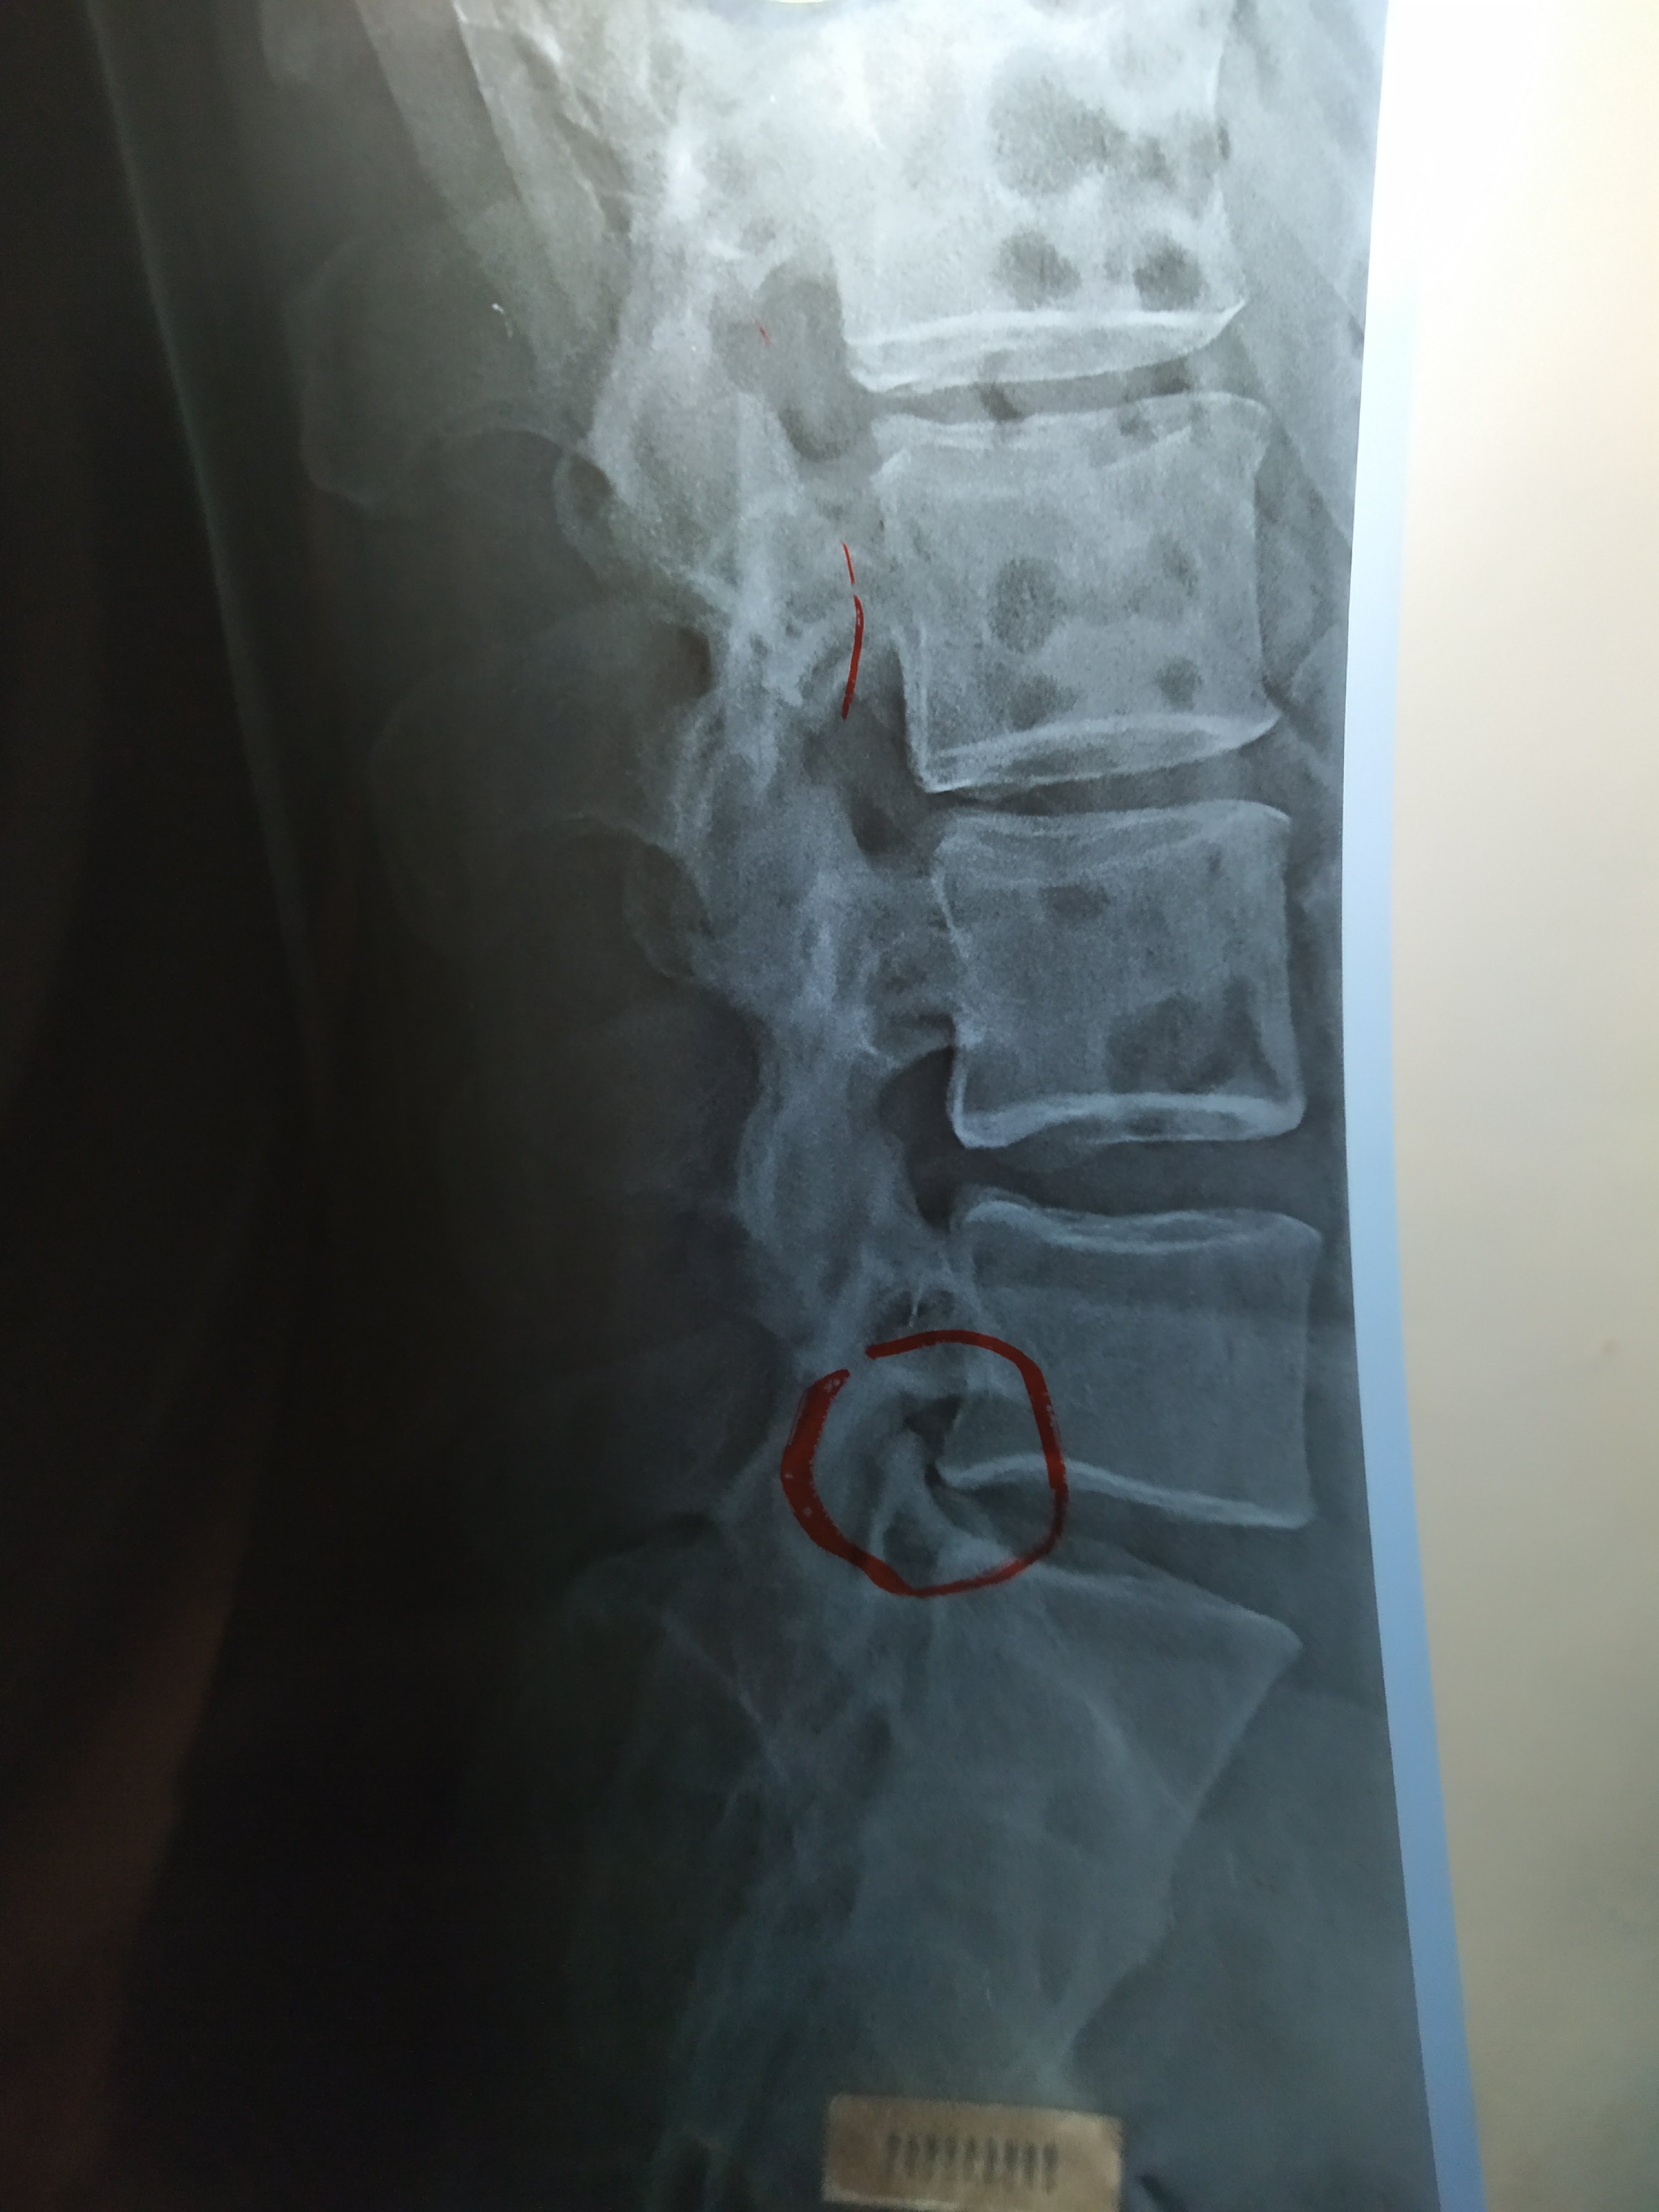

اشعر بالم اسفل الظهر وصعوبة بالحركة منذ ثلاثة أيام ومرفق صورة من الأشعة العادية على الفقرات القطنية

ارجو الافادة في وجود الام اسفل الظهر ومرفق صورة أشعة عادية على الظهر

الصورة تبدو طبيعية قد يكون تشنج عضلي يمكن استخدام مرخي عضلي مثل الكاريزول ومسكن متل الفولتافاست وكريم موضع بشكل تدليك خفيف متل الفولتارين جل مع الراحة